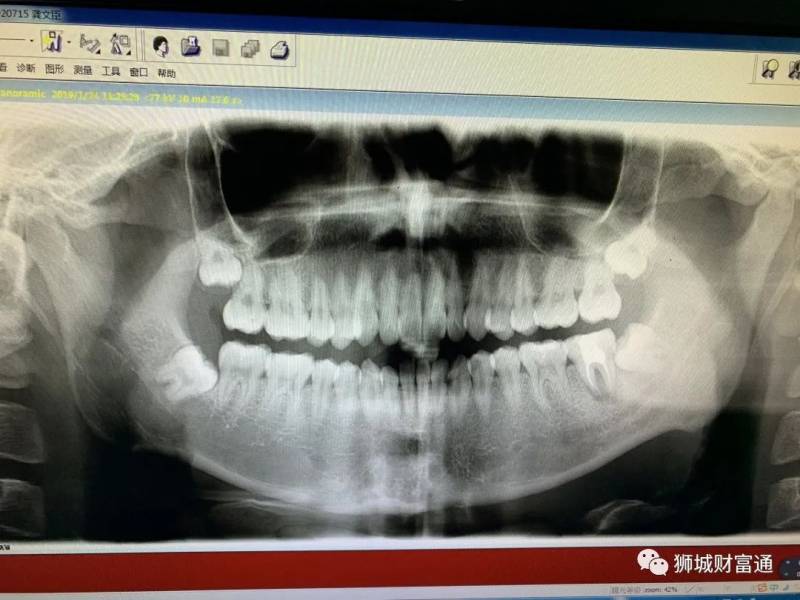

小编的智齿X光图

没想到回新加坡后,智齿又开始犯疼了,由于疫情的关系所以就去了新加坡本地的全民牙医诊所。在拍完X光后,这边牙医表示并不需要开刀,当场就把三颗智齿拔除了,整个过程花了大约一个小时左右。

同样是对三颗智齿进行诊断,新加坡牙医的诊断让我免受了开刀的风险。因此,小编觉得新加坡牙医的平均水平要高于国内牙医的平均水平。